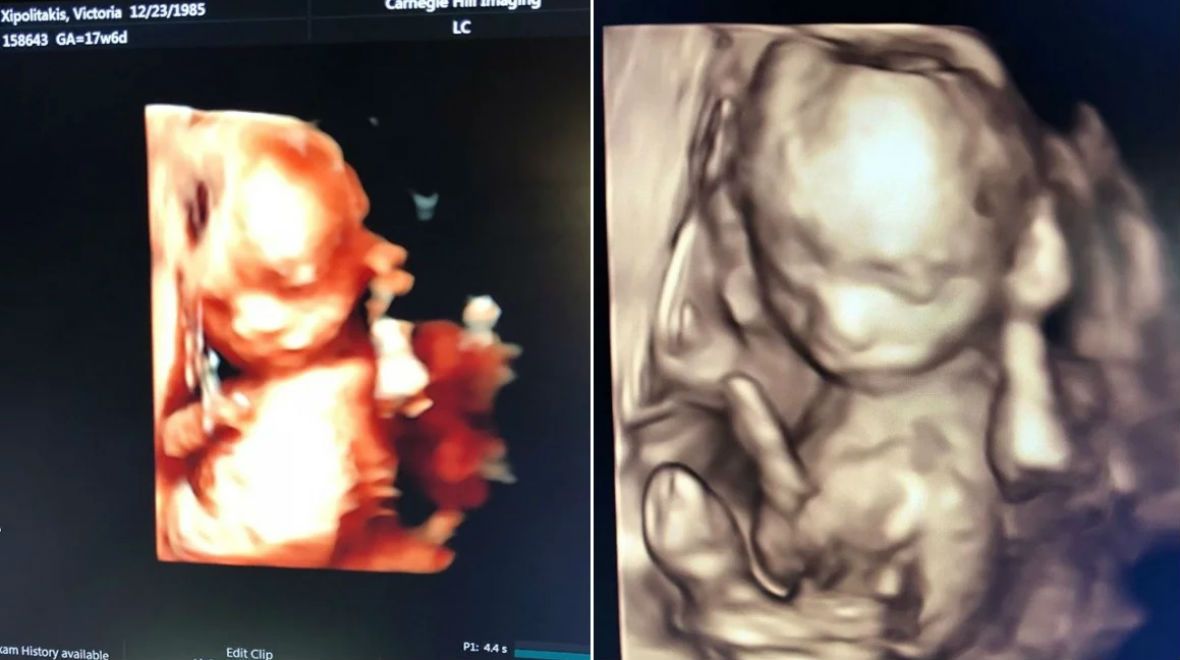

Vicky Xipolitakis mostró la ecografía 4D de su hijo

"Les presento al milagro de cuatro meses", expresó con mucha emoción la mediática en Instagram.

Lo cierto es que la mediática se encuentra embarazada y vive con mucha felicidad este momento. En Instagram, presentó la ecografía 4D de su hijo Salvador Uriel.

"Y con ustedes, les presento al milagro de cuatro meses @salvadorurielok", escribió en Instagram.

"¡¡¡Hoy cumple 18 semanas, ya mide como un pimiento y me regalo estas imágenes. Es la primera vez que le conozco la carita y no quería dejar de compartirlo con ustedes!!!! #SeMeExplotaElCorazónDeFelicidad. ¿¿Lo ven parecido a mí???? #HijoTeAmo #SalvadorUriel", cerró la rubia pura emoción.